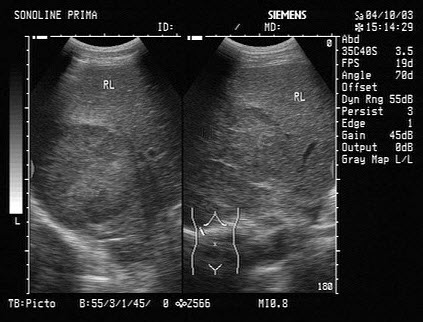

C.低置

D.部分性

E.以上都不是

48、单项选择题 当声频在20kHz以上的我们称为()

A.超声

B.次声

C.可听声